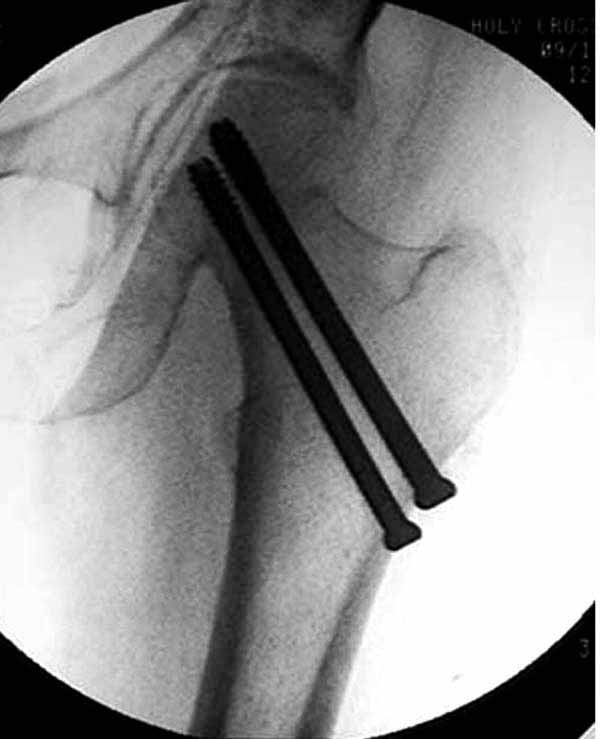

Пациентка Ш. 76 лет, 11 дней назад прооперирована по поводу вколоченного субкапитального перелома шейки левой бедренной кости, 3-мя канюлированными винтами. Вчера пациентка упала в палате. И вот результат- подимплантатный подвертельный перелом левой бедренной кости. Уважаемые коллеги, пожалуйста посоветуйте какой метод дальнейшего лечения предпринять дальше.Соматически пациента повышенного питания, страдает варикозной болезнью нижних конечностей.Из предложенных вариантов коллег - целллокастовая укороченная кокситная повязка, скелетное вытяжение сроком на 40-45 суток - отпали сразу, так как необходимо активизация пациентки.На данный момент рассматриваем следующие варианта реостеосинтеза:(наличие технических возможностей) 1. Длинная Gamma 3 Stryker (с предварительной интраоперационной фиксацией головки спицами).2. Трохантерный штифт DePuy с 2-мя метафизарными винтами в проксимальном отделе, (также с интраоперационной фиксацией головки спицами. Очень настораживает стабильность фиксации с проксимальном отделе с связи с выборкой костной ткани ранее находящимися там канюлированными винтами. Сейчас пациентка находится на скелетном вытяжении, с дисциплинирующим грузом. Операция планируется после праздников. Заранее извиняемся за качество и неполное соответствие проекций на R-ммах (R-служба отдельная песня). При интраоперационном ЭОП-контроле винты в аксиальной проекции разнесены по шейке.

1. винты расположены не в лучшем положении:

два в нижней части шейки. Более стабильная структура как раз обратная: два шурупа в проксимальной части шейки , и не дальше центральной части головки, иначе есть риск пенетрации. дистальный винт мог бы быть выше уровня малого вертела. Его дистальное расположение описано с увеличенным риском послеоперационного перелома.

Как отметили коллеги, необходимо обратить внимание на последовательность введения каннюлированных шурупов. Рекомендуется введение в форме “V”, т.е основанием вниз, потому что в другой последовательности за счет увеличения стресса латерального кортекса имеется риск перелома. За редким исключением удается установить Guide wire с первой попытки и многоразовые пробы спицей увеличивают стресс. Небольшая травма может привести к перелому.

Работа Burstein AH and Wright TM: Fundamentals of Orthopaedic Biomechanics. Williams & Wilkins, Baltimore, pp. 160-169, 1994 доказывает, что шурупы, введенные на уровне малого вертела или ниже, приводят к осложнению. Введенные шурупы под 135 и больше градусов в 20% осложнились подвертельными переломами бедра.